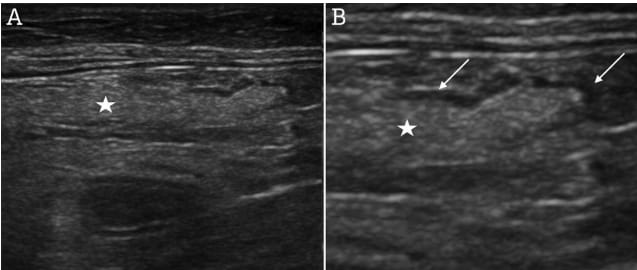

Longitudinal sonogram of jejunal lymph node lipomatosis obtained prior to euthanasia. The central hyperechoic area (stars) corresponds to the lipomatous tissue. In panel B, the image was magnified to optimize the visibility of the peripheral rim (arrows).

A 16-year-old neutered female European Shorthair cat with chronic kidney disease (stage II) and suspected hepatic lipidosis underwent abdominal ultrasound, revealing uniformly hyperechoic JLNs with thin hypoechoic peripheral rims. Power Doppler interrogation showed no vascularization. Two years later, the cat was euthanized for end-stage kidney disease, and jejunal lymph nodes were re-examined via ultrasound and histology. Histopathological evaluation included H&E and Oil Red O staining to confirm adipose tissue infiltration.

Postmortem ultrasound confirmed unchanged hyperechoic JLNs. Macroscopic evaluation showed JLNs embedded in mesenteric fat. Histologically, adipocyte infiltration replaced the lymphoid parenchyma, with residual thin subcapsular lymphoid tissue rim and peri-adipocyte lymphocyte cuffing. Oil Red O staining confirmed neutral lipid accumulation. No evidence of inflammation or neoplasia was found. Findings were consistent with benign lymph node lipomatosis. The cat’s history of suspected lipid metabolism dysfunction (hepatic lipidosis) and old age supported parallels with human cases.